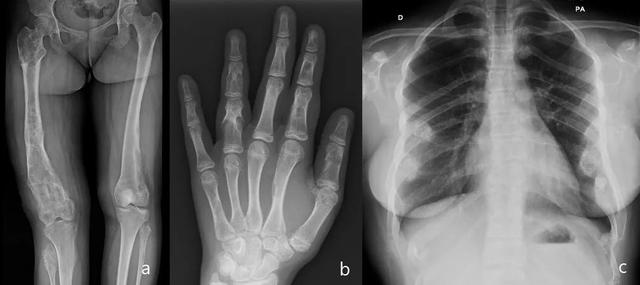

图12:多发性软骨瘤病或Ollier病。扩张性溶解性病变,主要位于身体右侧,股骨和胫骨和腓骨干骺端广泛累及,导致腿长差异(a)。软骨瘤位于手(b)的管状骨髓腔内的中央。多个软骨瘤涉及肋骨与软骨样钙化(环和弧形钙化模式)(c)。